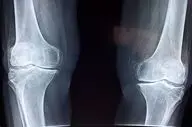

فوق تخصص بیماریهای روماتولوژی با اشاره به اهمیت پیشگیری و تشخیص زودهنگام پوکی استخوان گفت: این بیماری به کاهش مواد…